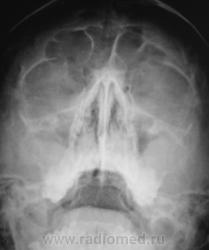

Пациент направлен оториноларингологом на рентгенографию придаточных полостей носа.

В центральной ячейке лобной пазухи - уровень жидкости - фронтит. в верхнечелюстных пазухах - картна кист, и сфеноидит...

Ячейки решетчатых костей с обеих сторон затемнены, имеются пристеночные теневые наслоения в обеих в/челюстных пазухах, больше у наружных стенок, , с четкими выпуклыми контурами, носовые ходы сужены. R-картина синуита. В наличии горизонтальных уровней в лобных пазухах сомневаюсь. А что бы определиться с основной пазухой, хорошо бы сделать боковую проекцию.

То же склонен видеть уровень жидкости в лобных (видно что повторяет наклон), пристеночное подушкообразное утолщение слизистой в верхнечелюстных, сфеноидит.

Согласна с коллегой по поводу сомнительности затемнения лобных пазух, это может быть обусловлено ячейками решетчатой кости.